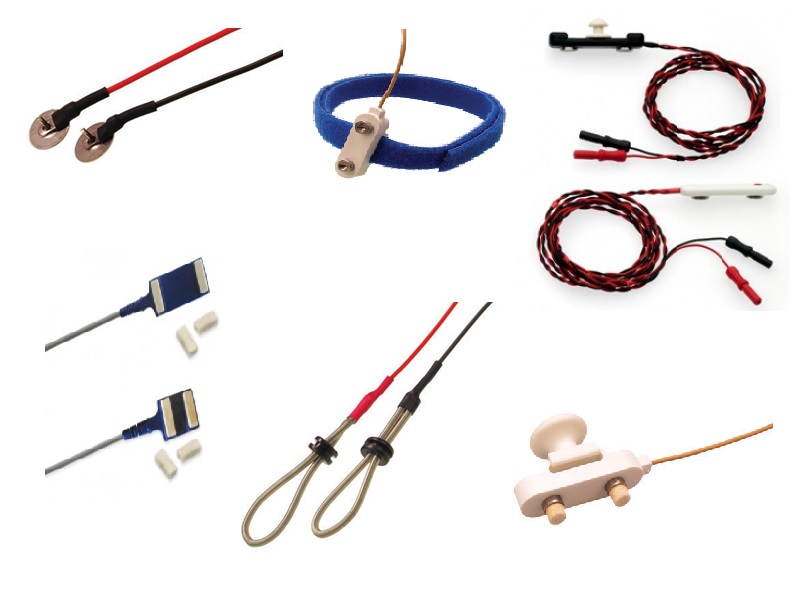

- Eletrodo de Concha

- Acessórios Estudos de Sono PSG

- Eletrodos de superfície descartáveis

- Eletrodos de estimulação e registro

- Eletrodos de terra